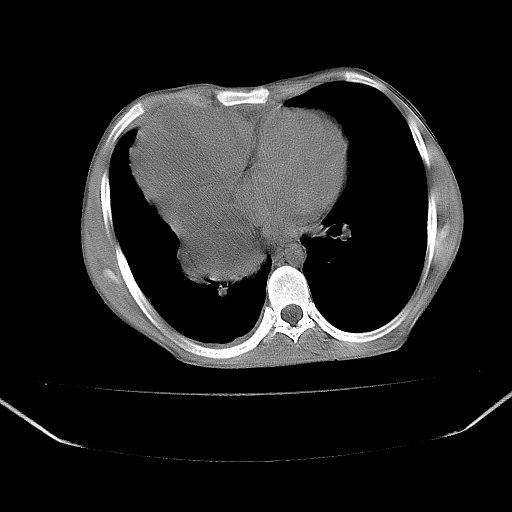

以下是引用zjzjr在2008-7-20 12:57:00的发言:[br]考虑为生殖源性肿瘤(内胚窦瘤),侵袭性胸腺瘤可能性大;右侧少量胸腔积液。

以下是引用xinliheng001在2008-7-20 21:17:00的发言:[br]右纵隔巨大分叶状软组织均质密度肿块,右上肺叶受压明显,纵隔右移、胸膜受累有少量积液和结节样增厚。应增强扫描一定会有更具诊断价值的信息。

以下是引用xinliheng001在2008-7-20 21:17:00的发言:[br]右纵隔巨大分叶状软组织均质密度肿块,右上肺叶受压明显,纵隔右移、胸膜受累有少量积液和结节样增厚。应增强扫描一定会有更具诊断价值的信息。